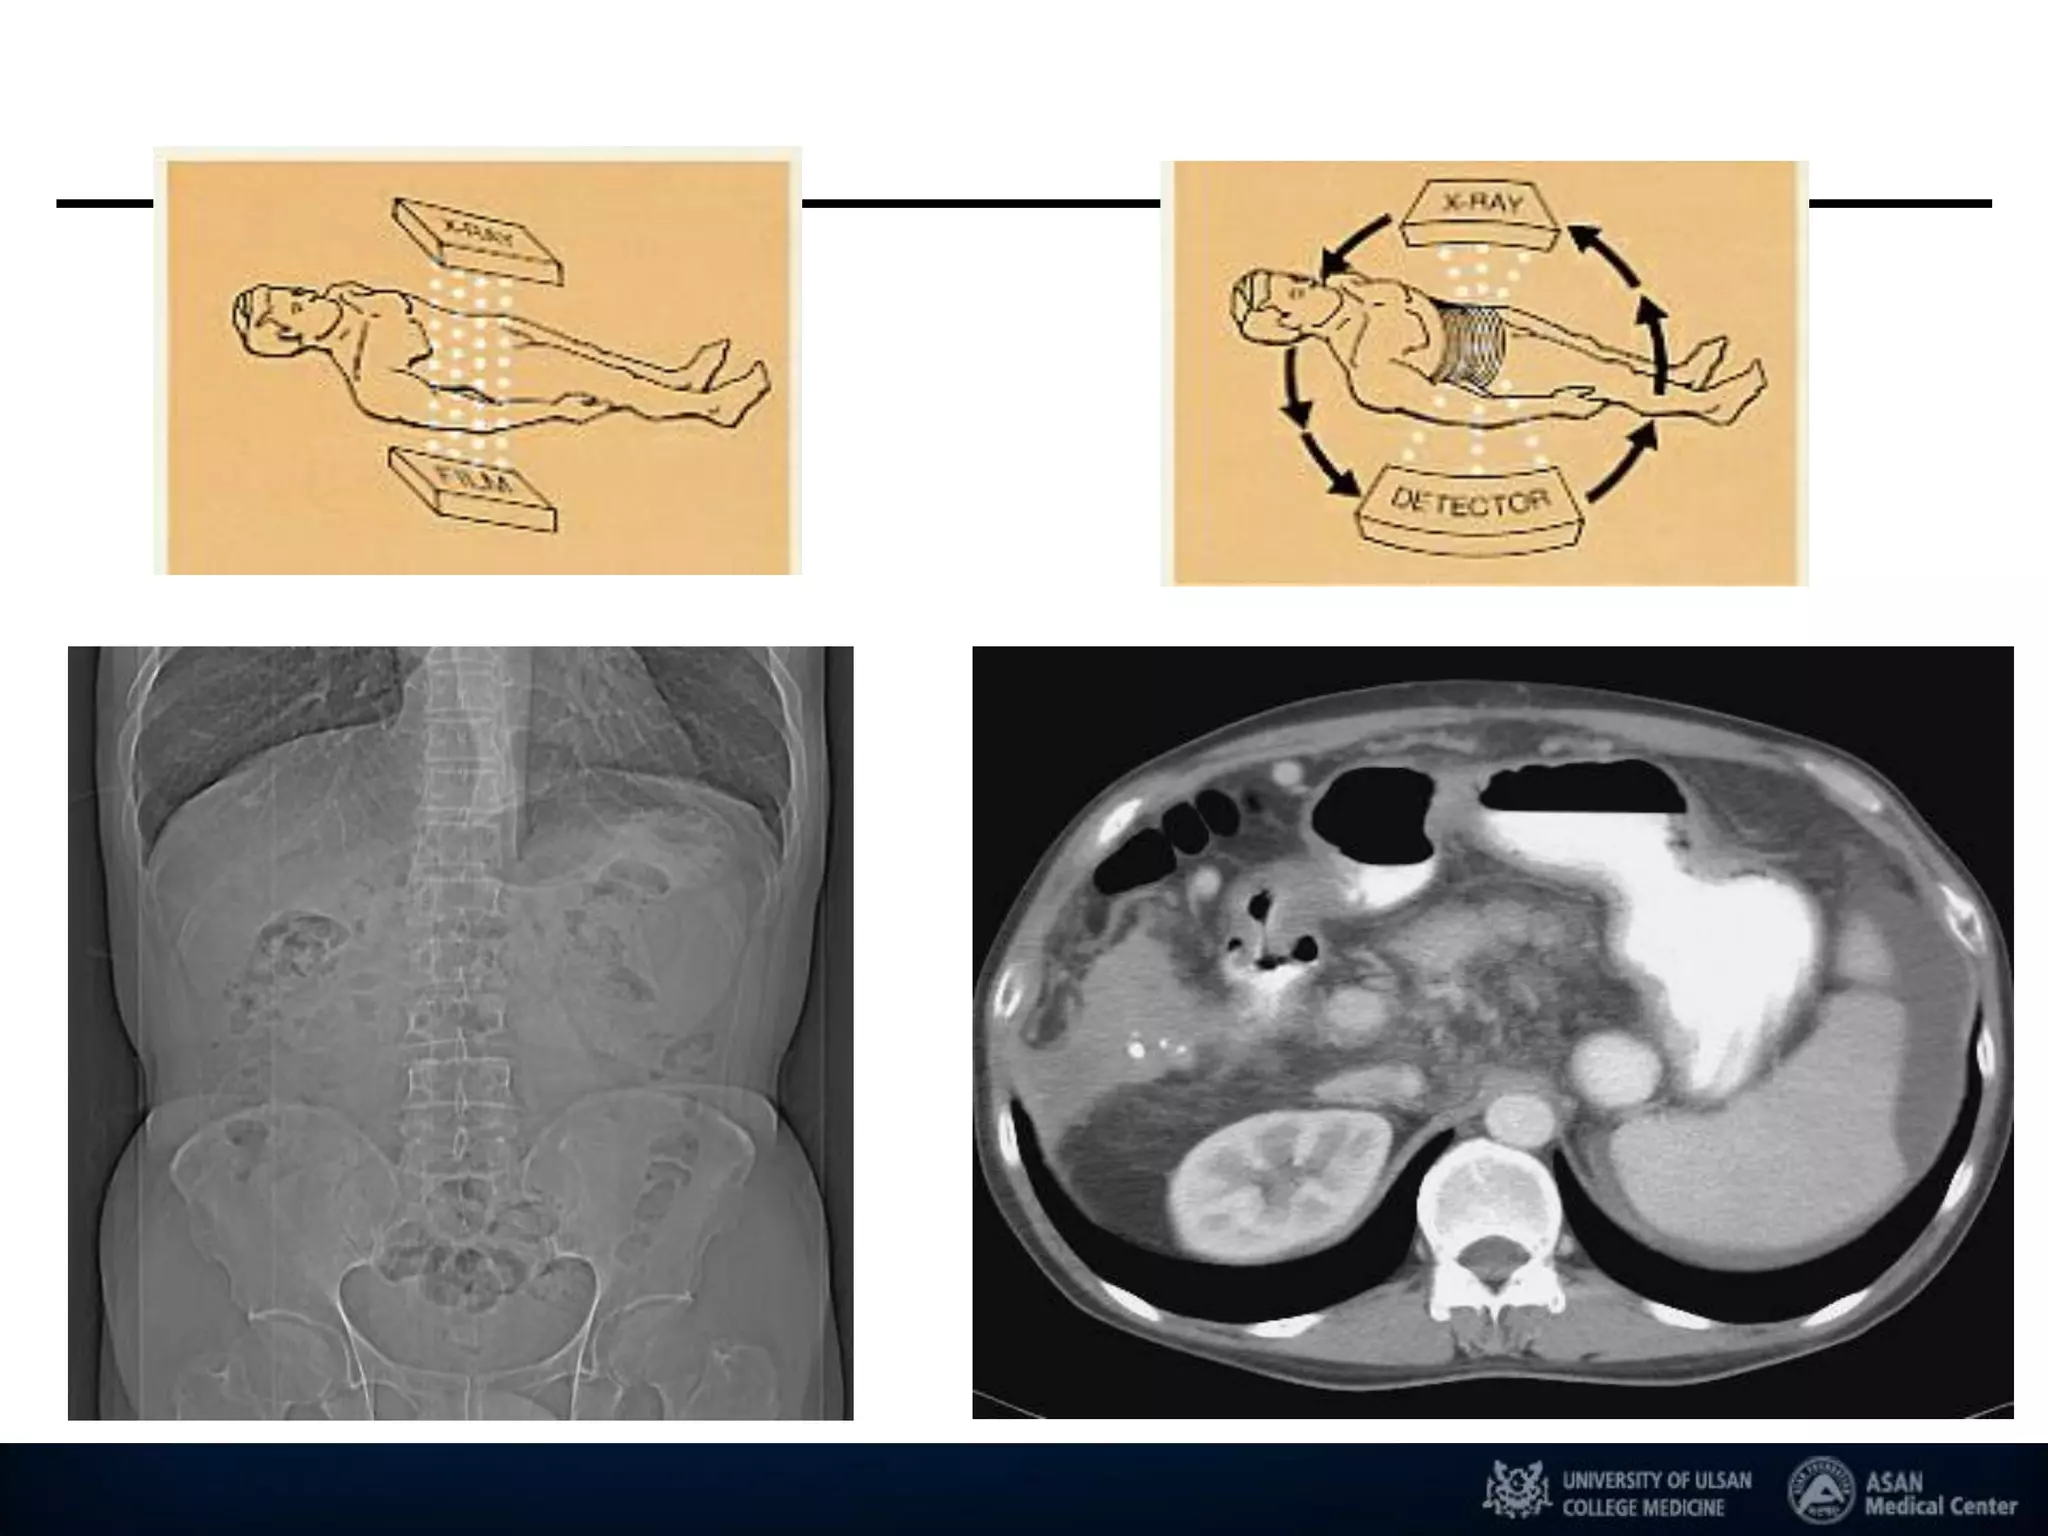

Imaging Revolutions : CT

기존 X-Ray의 단점